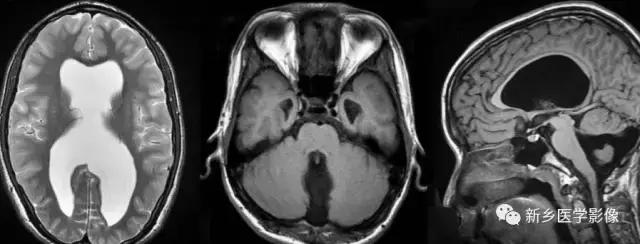

(2)脑裂畸形:胚胎期脑的发育经历6个主要阶段:①背侧诱导阶段;③腹侧诱导阶段;③神经增生阶段;④神经元移行阶段;⑤组织形成阶段;⑥髓鞘形成阶段。脑裂畸形发生在神经元移行阶段。脑裂畸形可累及一侧或双侧大脑半球,脑裂畸形位于侧面.常累及中央前、后回区偶尔位于大脑半球的其他部位。脑裂畸形的裂隙可以很窄,裂隙两侧灰质紧密相贴,称闭合型。裂隙也可以很宽,中间为脑脊液,分离型。

分离型脑裂畸形需要与脑穿通畸形囊肿鉴别.脑裂畸形的裂隙两旁一定为一灰质结构,而脑穿通畸形囊肿周围无脑灰质包绕。裂隙两旁是否为灰质结构是区别脑裂畸形与脑穿通畸形囊肿的可靠征象。裂隙两侧的灰质可不正常,可呈多小脑回样。脑裂畸形也可合并脑灰质异位。

分离型在CT很容易显示.闭合型有时容易漏诊.MRI对裂隙两侧的灰质结构容易辨认。脑裂畸形常合并透明隔缺如.侧脑室扩大,脑裂畸形处脑室边缘不规则.常可见指向裂隙的裂或 三角形憩室存在。

临床上脑裂畸形常表现有癫痫发作,其他神经系统症状可从很轻微到很严重.主要取决于脑裂畸形使脑组织缺损的严重程度。单侧闭合型脑裂畸形症状通常较轻,双侧分离型脑裂畸形症状较明显。